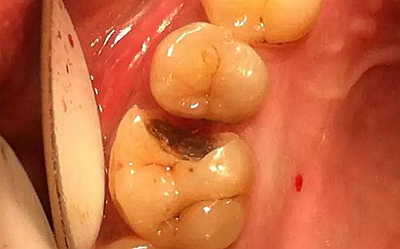

最后附幾例一次性根管治療+冠延長手術+高嵌體修復的病例,均為兩次完成。第一次就診:根管治療一次完成,后冠延長手術,然后高嵌體預備,取模,第二次就診,拆線,試戴嵌體。具體在此不做詳細說明,圖中有詳解。

另外一個病例

病例3